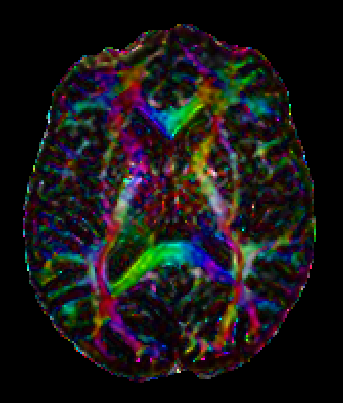

Colormaps What are they and what's the utility?

Colormap is, as the name suggest, a map between a variable and a color. In a 3D spatial context, the color is used to indicate a specific spatial direction, that is, a 3D spatial vector direction will be translated in a specific color. To find a correlation that bring value to the desired spatial visualization is a challenging task to designers and final users, because different choices may enhance different aspects. Below we propose a series of visual representations of different colormaps, each one is rendered in a sphere where the normal vector of a point in the surface represent the spatial direction considered on the map.

Absolute value Colormap

In this colormap the absolute value of the three component of the 3D Spatial vector (x,y,z) is translated into RGB colors. It is the most one used. Its color variation in orientation is smooth, but there is a serious problem with ambiguity in spatial orientation, that is, more than one direction is mapped onto the same color.